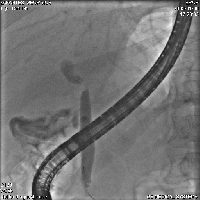

Πρόκειται για άνδρα ασθενή 62 ετών, ο οποίος υποβλήθηκε σε αξονική τομογραφία (εικόνα 1) για άτυπα γαστρεντερικά συμπτώματα και υπερχολερυθριναιμία. Διαπιστώθηκε μάζα μεγέθους 2,5 cm στον αριστερό (τμήμα 4) λοβό του ήπατος, η οποία εξορμούνταν από το χοληφόρο δένδρο, καταλάμβανε τη συμβολή του δύο ηπατικών πόρων, καθώς και το κεντρικό στέλεχος του αριστερού ηπατικού πόρου (χολαγγειοκαρκίνωμα τύπου Klatskin IIIB). Διενεργήθηκε ERCP (εικόνα 2) για τοποθέτηση παροχετευτικού stent και διόρθωση της υπερχολερυθριναιμίας. Υποβλήθηκε σε τυπική αριστερή ηπατεκτομή (τμήματα 1, 2, 3 και 4), εκτομή του εξωηπατικού χοληφόρου δένδρου έως τη Β' διαίρεση του δεξιού ηπατικού πόρου (εικόνα 3), καθώς και σε πλήρη λεμφαδενικό καθαρισμό του ηπατοδωδεκαδακτυλικού συνδέσμου (st 12A και st 12B). Η εντερική αποκατάσταση διενεργήθηκε με ηπατικονηστιδοστομία και με έλικα Roux μήκους 60 cm (εικόνα 4). Μετά την 4η μετεγχειρητική εβδομάδα, δόθηκε χημειοθεραπεία βασιμένη στο gemcitabine. Ο ασθενής παραμένει ελεύθερος νόσου.